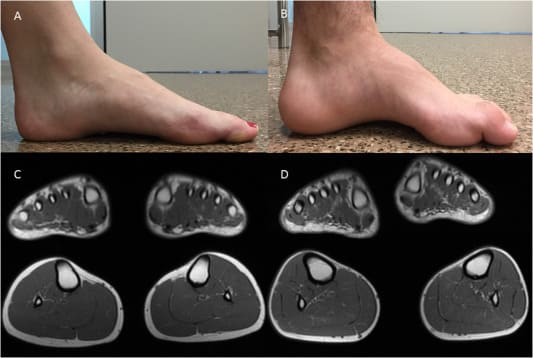

CMT 질환은 신경 손상을 일으키는 유전성 질환의 집단이다. 일반적인 증상은 다리와 발의 허약함, 근육량 감소, 발가락이 오그라드는 것이다. 비록 CMT가 가장 흔하게 유전되는 신경 질환 중 하나이긴 하지만 -- 약 3,000명 중 한 명에게서 발견되지만, 아직 그것에 대한 승인된 치료법은 없습니다.

DGIST의 김민석 신임 생물학 교수가 이끄는 연구팀은 쥐 모델에서 신경 주위에 형성되는 절연과 보호막인 미엘린을 재현할 수 있는 특정한 전기 자극 조건을 발견했다.

연구원들은 전기 자극이 미엘린 막의 단백질과 콜레스테롤 분포의 이상을 개선시켰다는 것을 발견했다. 전기자극치료 3주 후 CMT로 인해 감소했던 마우스의 운동능력은 마우스의 손상된 미엘린이 회복되면서 향상되었다.